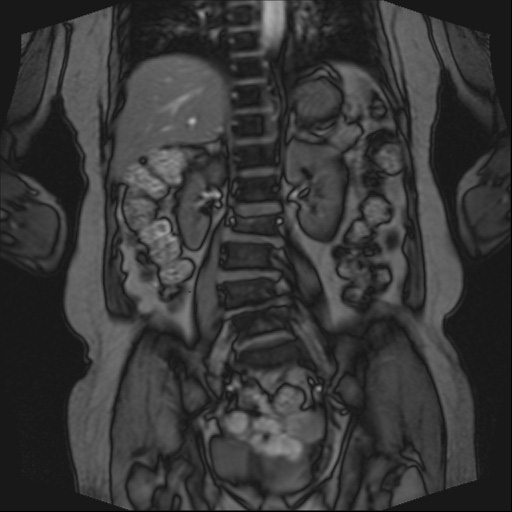

Ӵϲ ɿ ô ô 㸮 ٸ ̾ϴ. ϵ Ͻð ܻ 㸮 20⵿ ͽϴ. mri ˻ ɿ Ȳ ʹ ؼ Ȳ̶ ߽ϴ. ϻȰ ϰ 鼭 ½ϴ. ̴ ø鼭 Ͻô Ȳ ̷ ġ ص ȸ ϴ. δ Ҵµ, ù ȸԲ ˷ֽ ϰ β ϰ, ˷ֽ ü ƮĪ ϸ鼭 ȭǸ鼭 Ӵϲ ȸų ְ ǰ, β 鼭 ʴ β ؾϴ ŷο 1ϸ ijħ ڸ ǥ Ʈ ߽ϴ. ȸ ȭϽø鼭 Ϸ簡 ٸ ȸǽð 4ְ Ǿ Ǯ鼭 ¦ ҽϴ. ħ ȸ ȭϸ鼭 ڼ ü ƮĪ ϴ. ȥڼ Ͻʴϴ. ٳø鼭 ó Ͻ ʴϴ. ̾ ְ ̳ ߵ ʰ ϴ ȸԲ Ͻʴϴ. ʹ ϸ鼭 ϴ. Ȩ - ϱ ٴ Ȳ MRIԴϴ. |